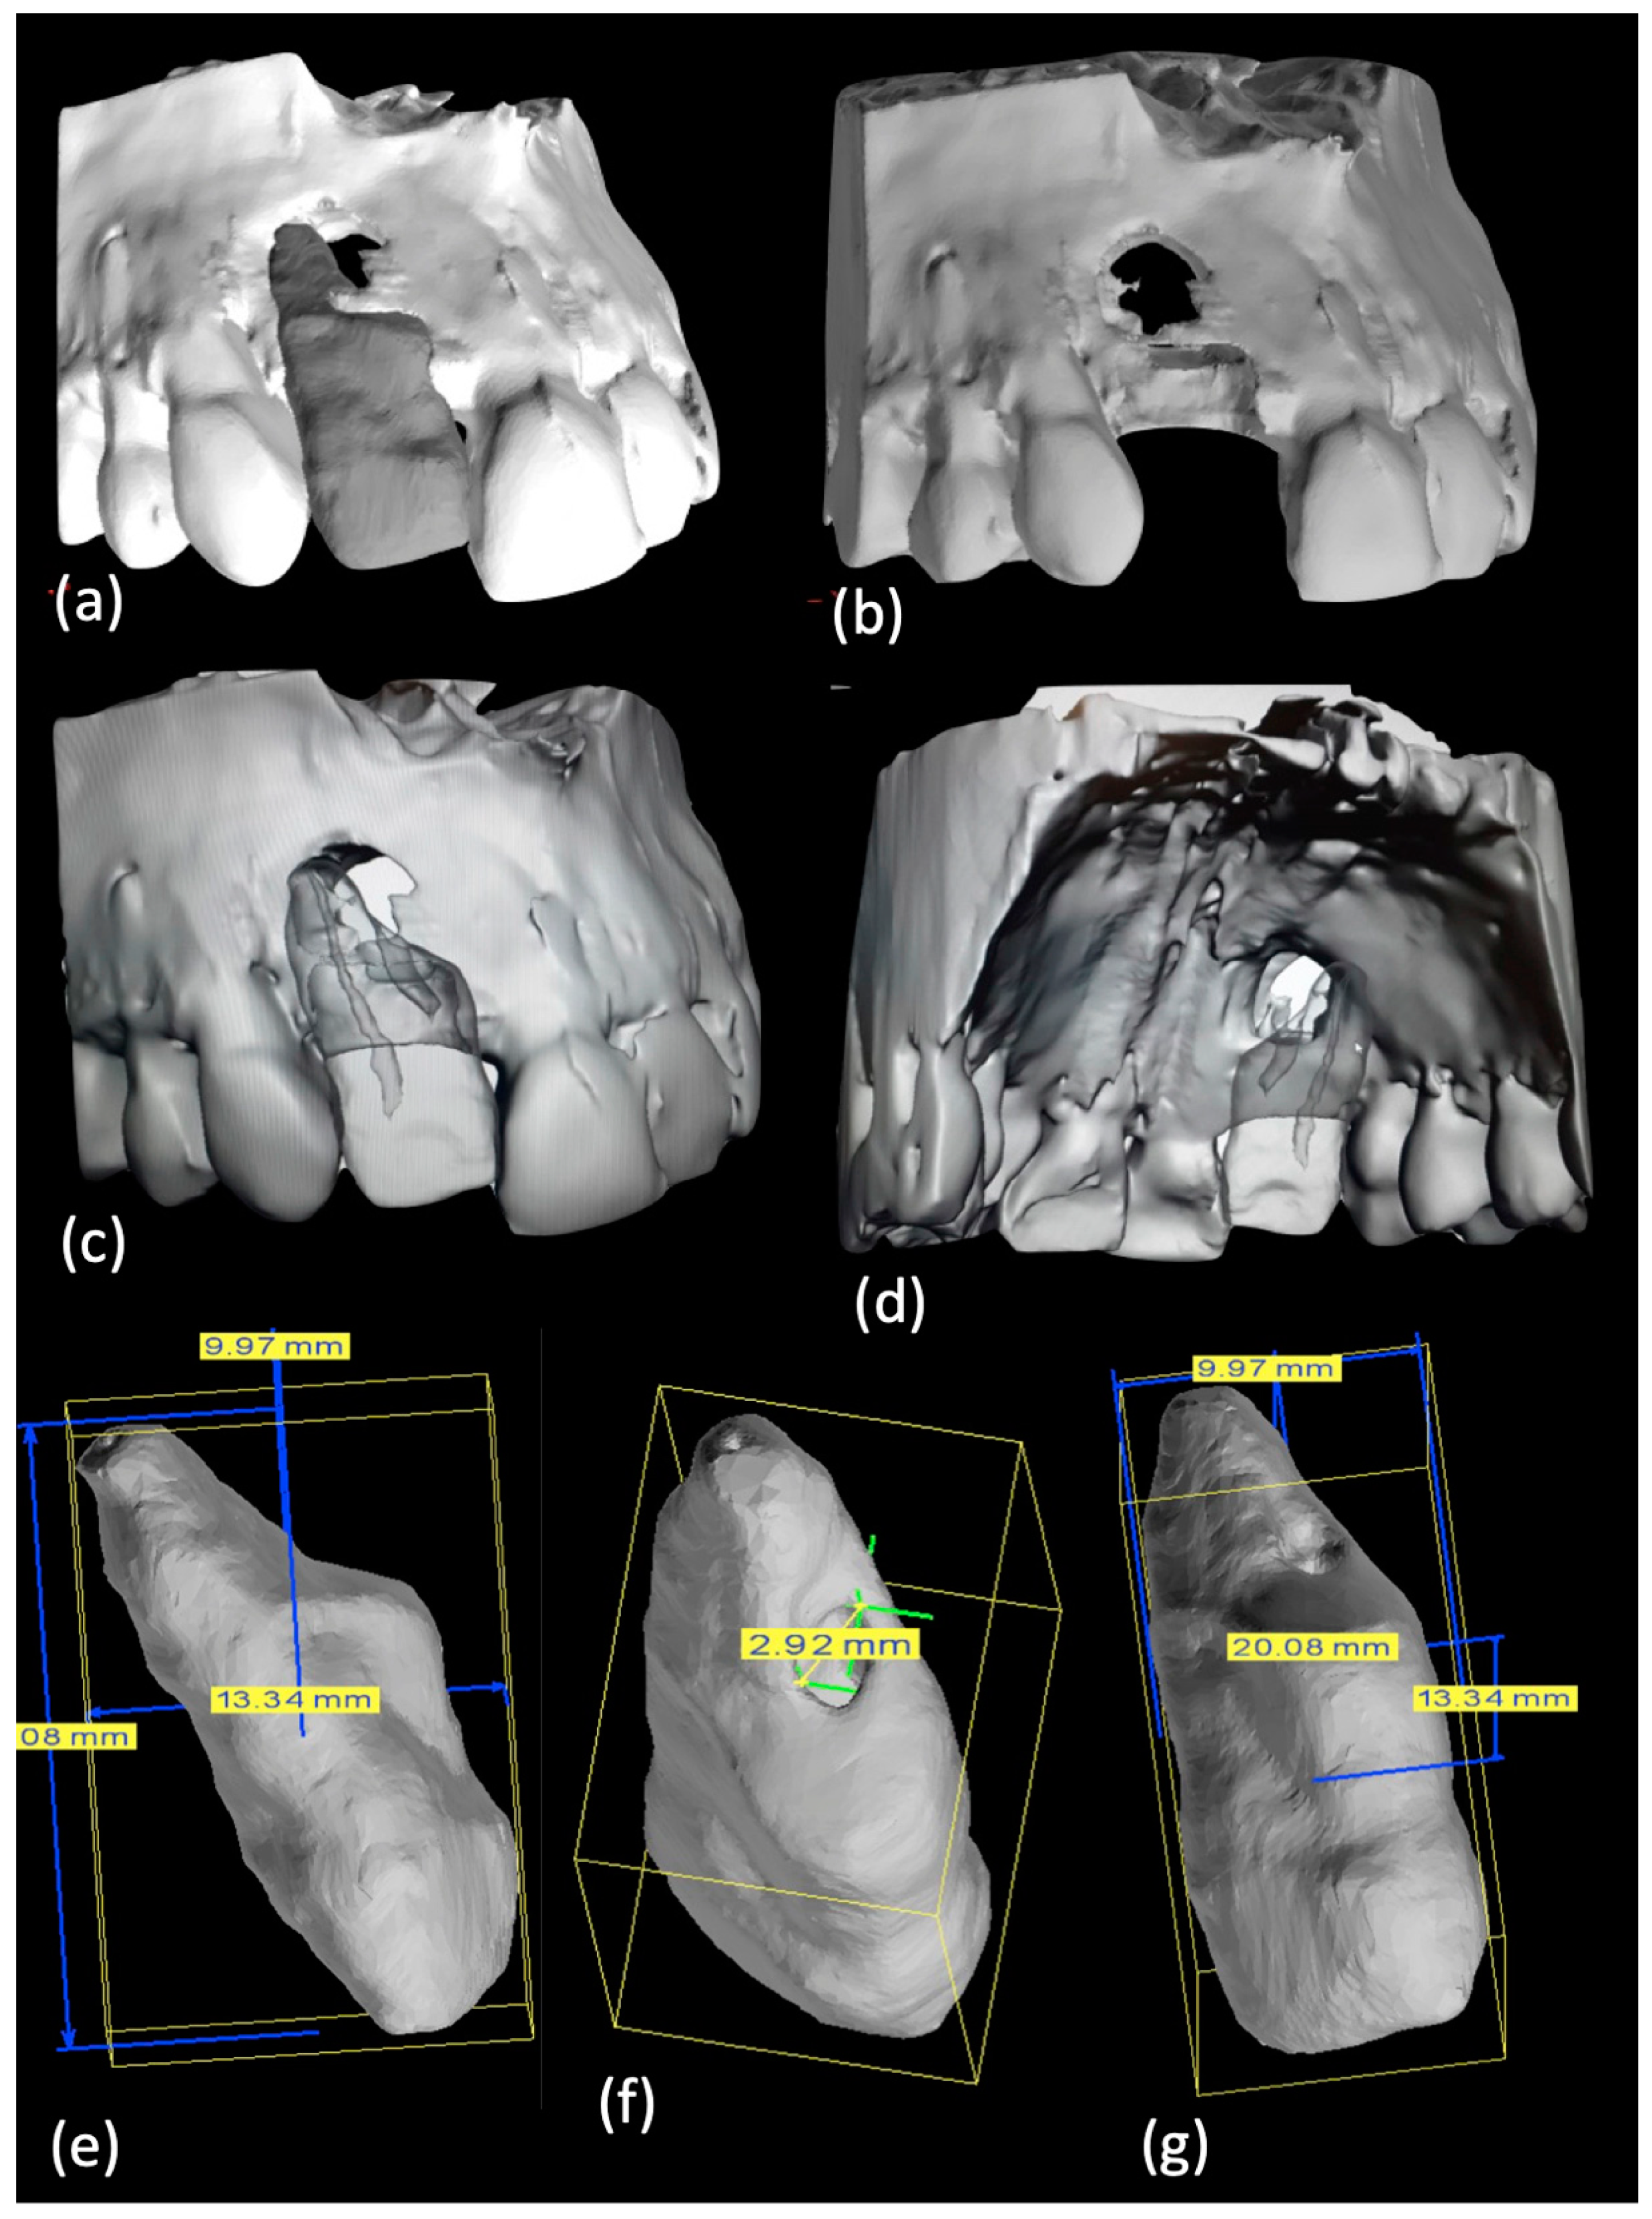

Print and Try technique and treatment planning: The CBCT file was transformed in an STL one. On the STL file the bone structure was previewed with and without the tooth (Figure 2a–d–Movie 2) and tooth dimensions, including the invagination size, were measured (Figure 2e–g).

Figure 2.

(a–d) An STL of bone structure with and without element 1.2 was produced and (e–g) dimensions of element 1.2 were achieved.